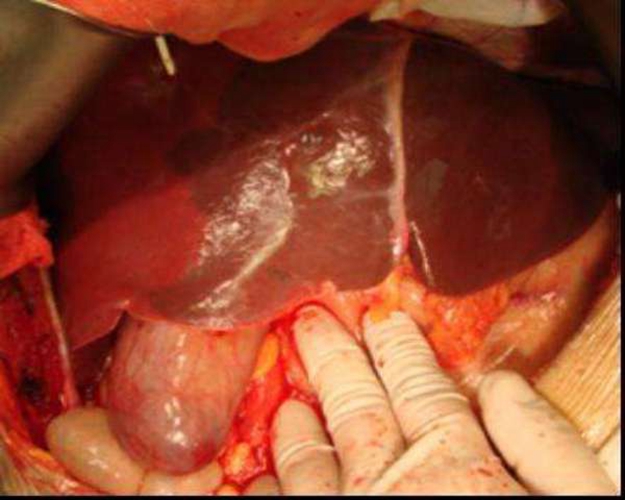

膽管癌圖片

肝外膽管癌

肝外膽管癌初晚期

肝外膽管癌黃疸表現